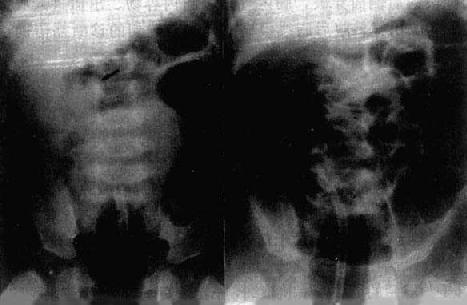

(一)腹腔积气 正常腹腔内,脏、壁层腹膜之间无气体存留。若因某种病因导致腹内积气且随体位改变而游动,该气体则称游离气腹。立位透视,气体可上浮到膈与肝或胃之间,显示为透明新月形气影(图4-1-1)。侧卧水平位投照,气体则浮游到靠上方侧腹壁与腹内器官外壁之间。仰卧前后位时,气体浮聚于腹腔前方,也可使居前方的肝镰韧带和器官外壁得到显示。局限性气腹,其腹腔内气体则局限于某处,且不随体位改变而移动。

图4-1-1 气腹两侧膈下见游离气体(↓)